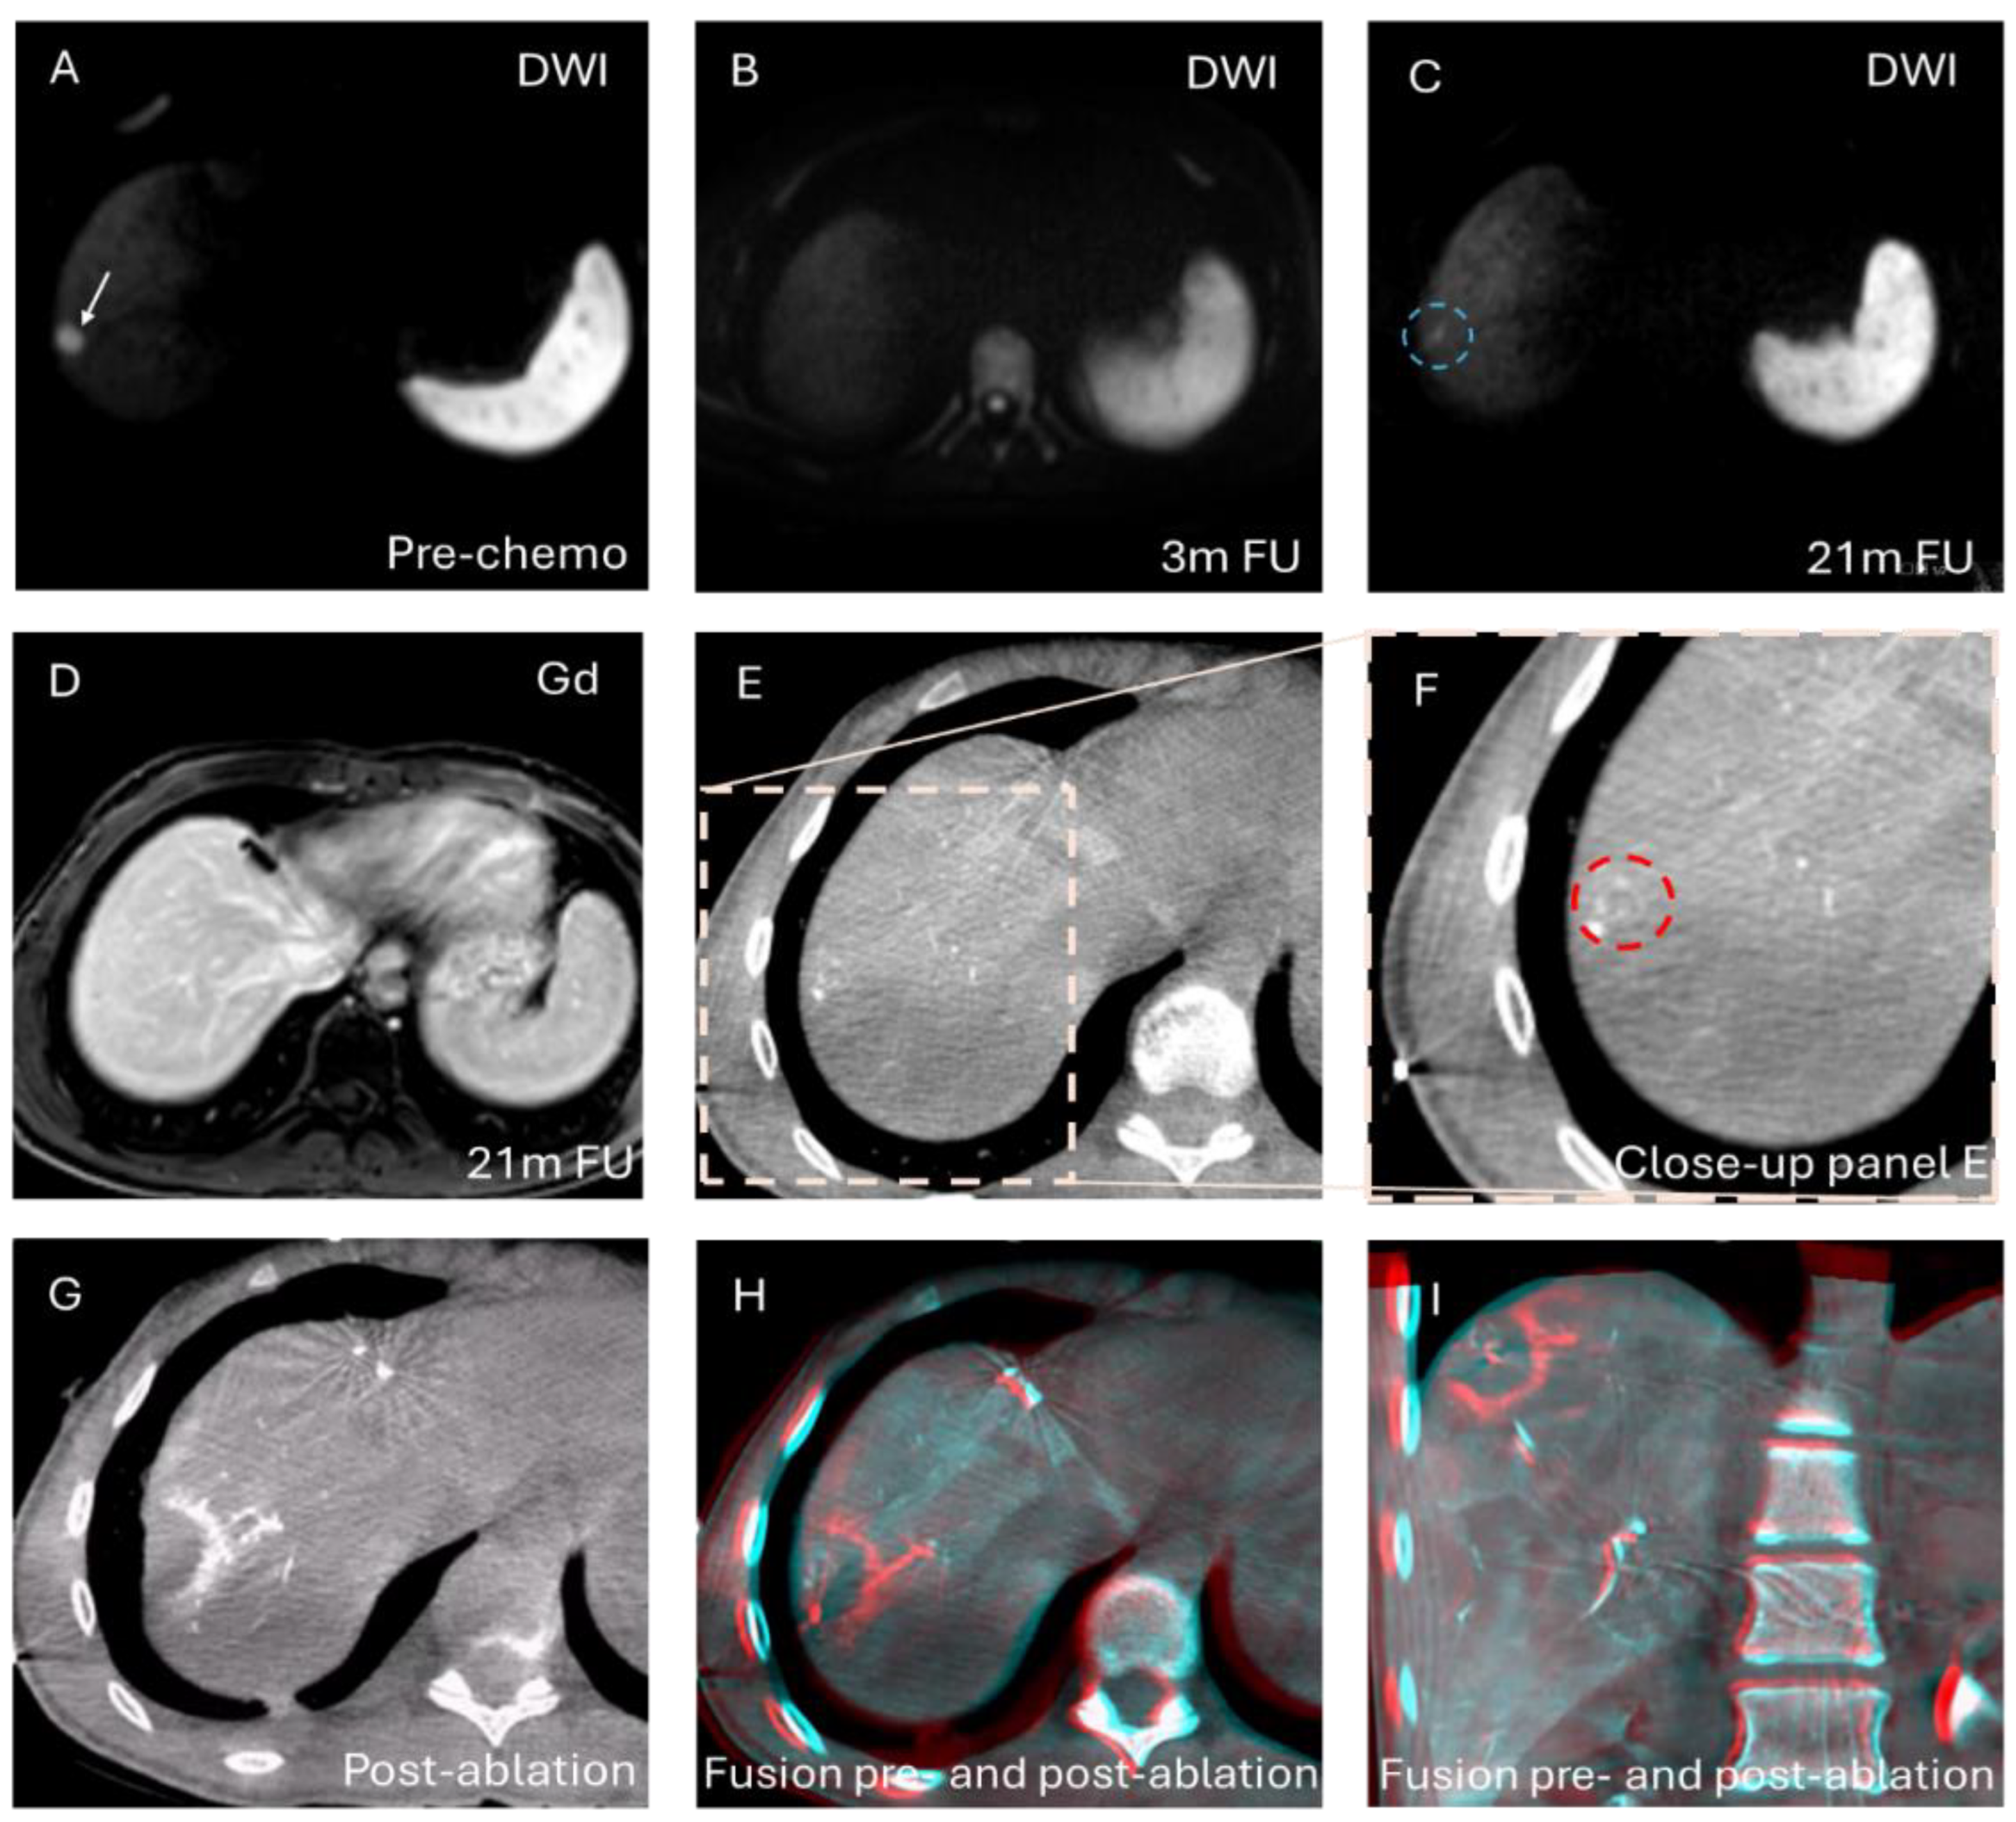

2.3. Imaging Protocol

2.4. Ablation

2.5. Study Objectives

2.5.1. Technical Success

3.2. Technical Success

3.3. Local Tumor Progression